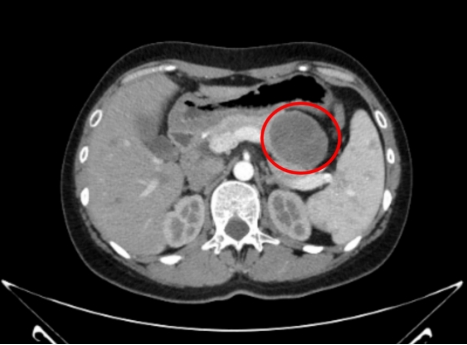

谭女士因上腹部轻度不适,到我院就诊,经检查发现胰腺体尾部有一囊性肿瘤,直径4.5厘米,需要进一步手术治疗,经我院普外二区副主任、副主任医师巢江玲详细解释病情,随即将谭女士收治入院。